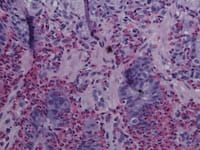

The Consortium of Eosinophilic Gastrointestinal Disease Researchers (CEGIR) is dedicated to improving the lives of individuals with eosinophilic gastrointestinal disorders through innovative research, clinical expertise and education via collaborations between scientists, health care providers, patients, and professional organizations. CEGIR is part of the Rare Diseases Clinical Research Network (RDCRN) and has a contact registry. Consider joining today. Read More